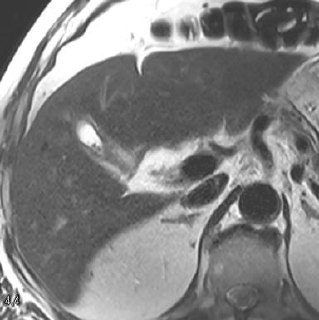

Редко их вижу, но вчера попалась добавочная доля печени🤓